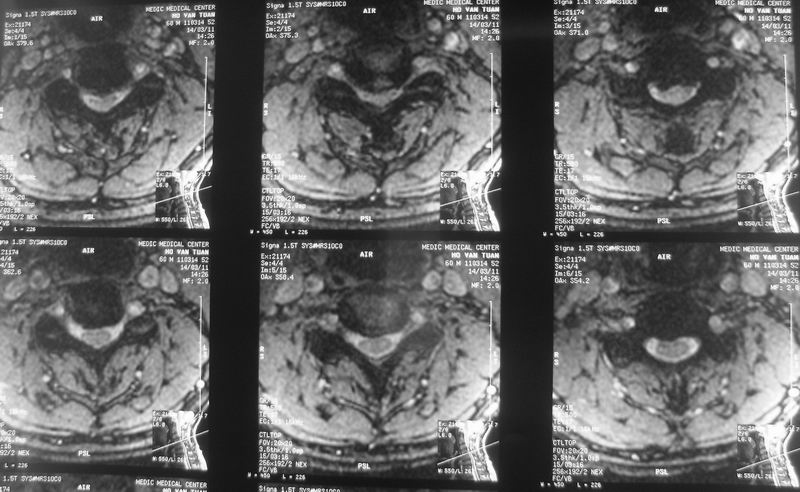

13-4-2011 C3-4 DH

A 60 Year -old male, 3 years with legs weakness, R arm pain. Poster longitudinal ligament was hypertrophy at mutiple levels.

6/6/2011, post- operation,